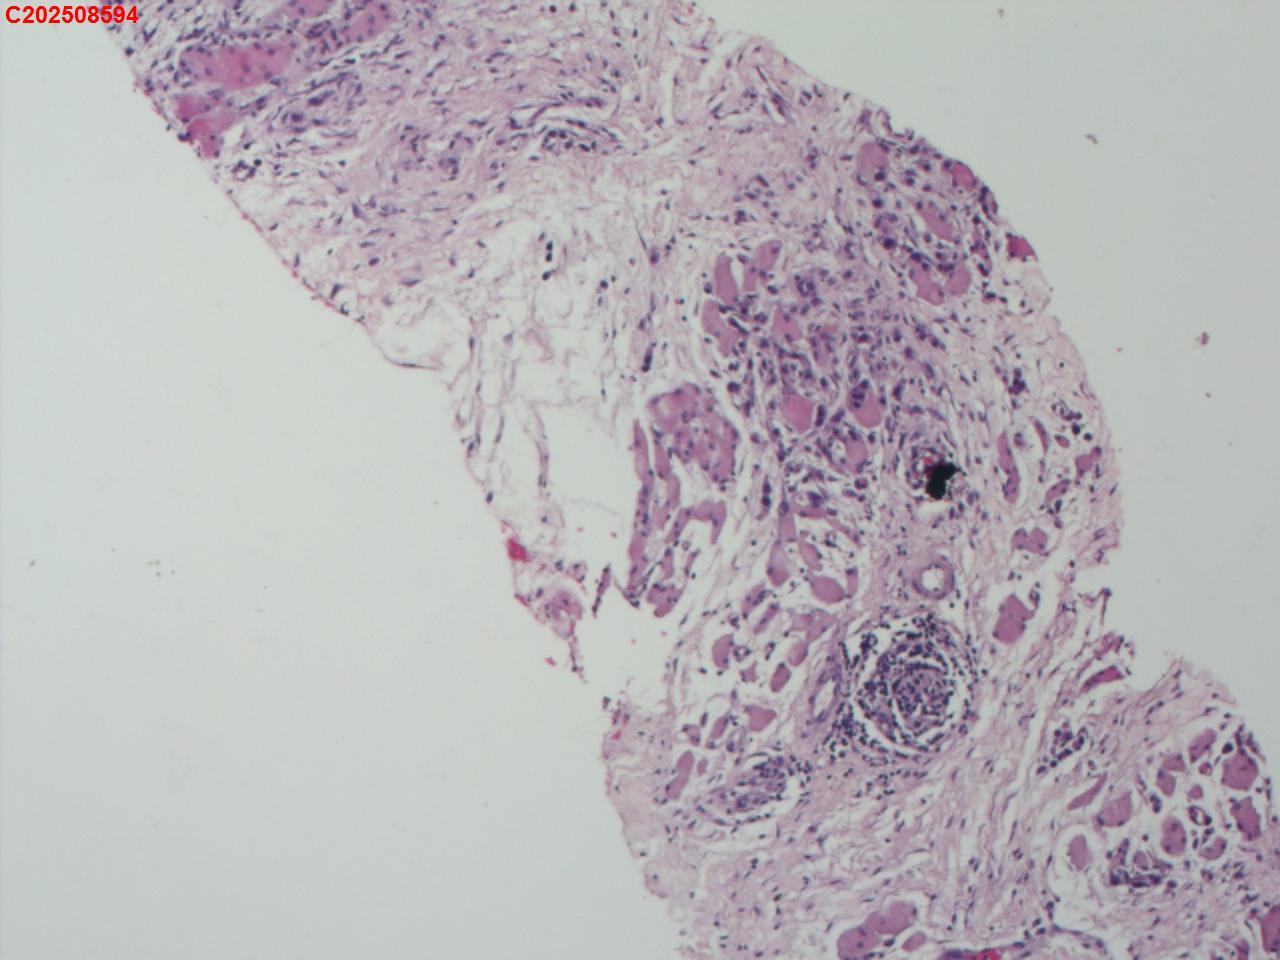

腰椎椎旁穿刺组织

性别年龄50岁临床诊断腰椎椎旁脓肿性质待查?

一般病史腰椎椎旁脓肿性质待查?

标本名称腰椎椎旁穿刺组织

大体所见腰椎椎旁穿刺组织2条

患者缘于入院前3个月无明显诱因出现腰腹痛,起初为隐痛,间断对症治疗,症状进行性加重,故入院前20天于某市第五医院就诊,查腰椎X片提示腰椎骨质增生,给予布洛芬、双氯芬酸钠等对症治疗,症状仍进行性加重,疼痛级别为5级,休息不能缓解,故入院前5天于某市第一人民医院就诊,查腰椎CT提示腰椎间盘膨出,腰椎退行性变,双侧腰大肌及背侧肌群增粗模糊致左侧输尿管下段粘连,尚短输尿管及肾盂扩张积水,腰背部皮下积液,嘱其回当地医院治疗,故入院前2天于某县中医院查彩超提示左侧腹腔内低回声包块,双肾积水、双侧输尿管上段扩张,右肾多发结石,遂于某市第二医院住院治疗,住院期间查CT提示双侧腰大肌及髂腰肌增厚、肿胀,左肾及输尿管腹段积水改变,腹膜后及左侧腹股沟区稍大淋巴结,左肺上叶及右肺中叶条索,胆囊多发结石子宫切除术后改变;血糖、肝肾功能、血脂基本正常,考虑腹腔结核可能。

描述诊断,未见结核病灶